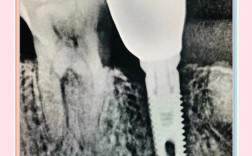

种植牙对骨量的要求远高于传统修复方式,牙齿缺失后,牙槽骨会因失去咀嚼刺激而逐渐吸收萎缩,尤其是缺牙时间较长、牙周病严重或外伤导致的骨缺损,骨量往往无法满足种植体的植入需求(通常需要种植体长度至少8-10mm,周围骨宽度至少3-4mm),20年前,由于术前检查手段有限,医生主要依赖普通X光片(如根尖片、曲面断层片)评估骨量,这些二维影像无法精确显示骨量的三维形态,容易低估骨缺损程度,导致术中发现骨量不足时不得不临时植骨。

20年前的种植体表面处理技术相对简单,多为纯钛光滑表面或简单的喷砂处理,其骨结合效率(即种植体与骨组织结合的速度和稳定性)远低于现在的SLA(喷砂酸蚀)或亲水表面技术,这意味着,即便骨量勉强满足植入条件,若骨密度较低(如骨质疏松、废用性萎缩的骨组织),种植体也难以获得初期稳定性,容易松动失败,医生往往倾向于通过植骨增加骨量,为种植体提供更稳固的“土壤”,提高骨结合成功率。

即刻种植的骨量要求

即刻种植(拔牙后立即植入种植体)在20年前技术尚不成熟,仅适用于拔牙窝骨壁完整、无明显吸收的情况,若拔牙后存在骨缺损(如根尖残留、骨壁穿孔),需同期植骨填充拔牙窝,否则种植体周围易形成血肿,影响骨结合。